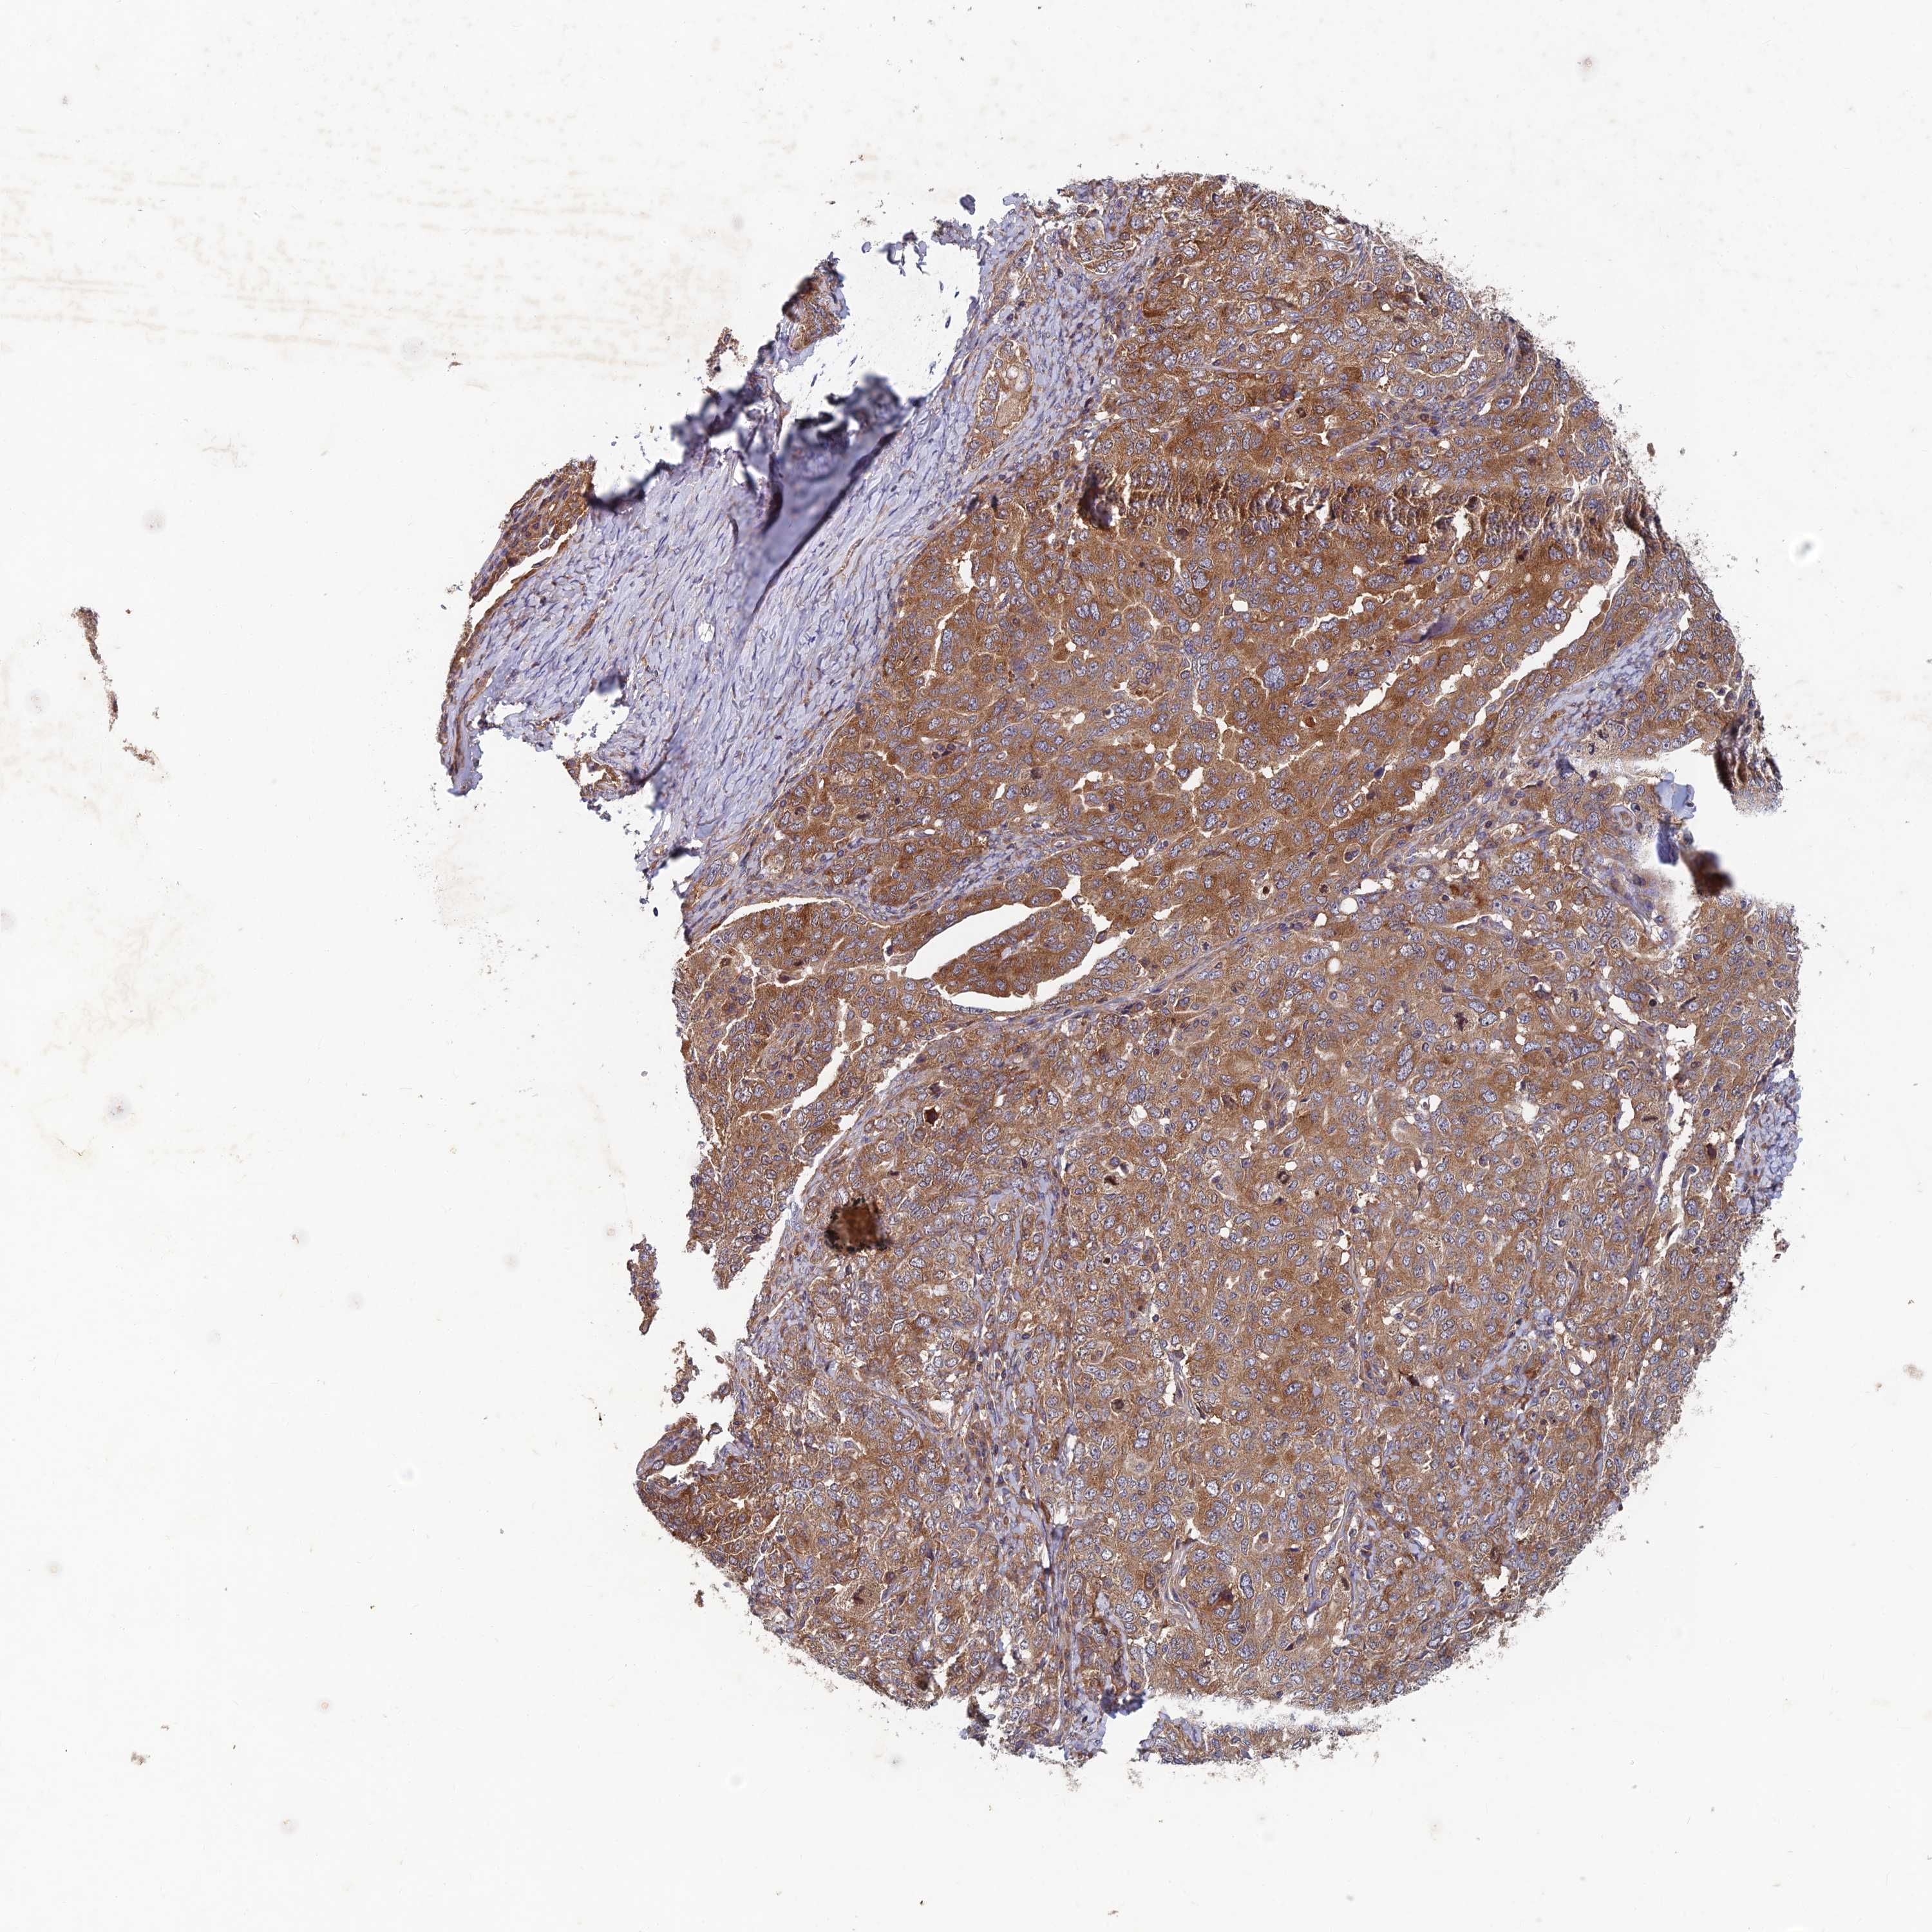

OVARIAN CANCER - Protein expressioni

A mouse-over function shows sample information and annotation data. Click on an image to view it in a full screen mode. Samples can be filtered based on level of antibody staining by selecting one or several of the following categories: high, medium, low and not detected. The assay and annotation is described here.

Note that samples used for immunohistochemistry by the Human Protein Atlas do not correspond to samples in the TCGA dataset.

Antibody stainingi

Antibody staining in the annotated cell types in the current human tissue is reported as not detected, low, medium, or high, based on conventional immunohistochemistry profiling in selected tissues. This score is based on the combination of the staining intensity and fraction of stained cells.

Each image is clickable and will lead to virtual microscopy that enables deeper exploration of all samples and also displays staining intensity scores, fraction scores and subcellular localization as well as patient and tissue information for each sample.

Antibody HPA039613

Staining

High

Medium

Low

Not detected

Intensity

Strong

Moderate

Weak

Negative

Quantity

>75%

75%-25%

<25%

None

Location

Nuclear

Cytoplasmic/membranous

Cytoplasmic/membranous,nuclear

Cystadenocarcinoma, serous, NOS

Carcinoma, endometroid

Cystadenocarcinoma, mucinous, NOS

Carcinoma, NOS